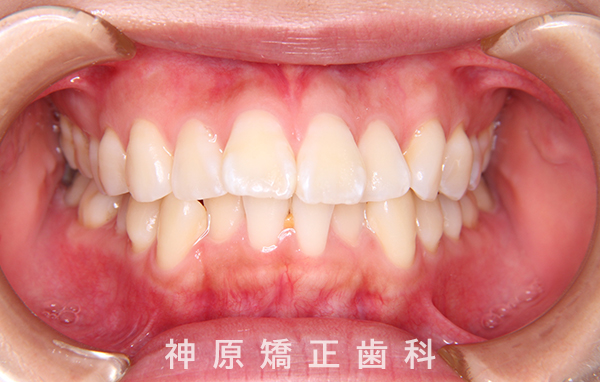

治療終了

口元の突出感と下の歯並びの乱れを改善するため、小臼歯を抜歯することにしました。抜いたスペースを利用して、前歯をできるだけ後ろに移動させるため、上下に歯科矯正用アンカースクリューを使用する計画を立てました。治療の目標について同意を得た後、矯正治療を開始しました。歯の動きが順調で、1年9カ月で治療が完了しました。その結果、側貌はE-lineに調和したバランスの良い仕上がりになりました。